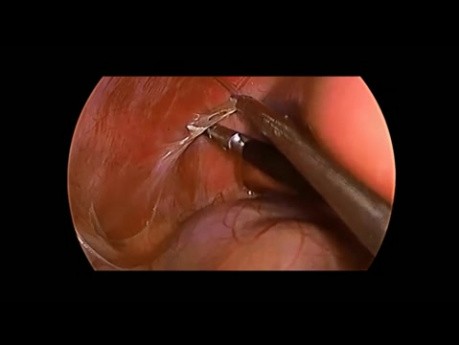

Colecistectomía laparoscópica en niño con curso...

El video presenta una colecistectomía laparoscópica en un niño con un curso inusual de la arteria cística.